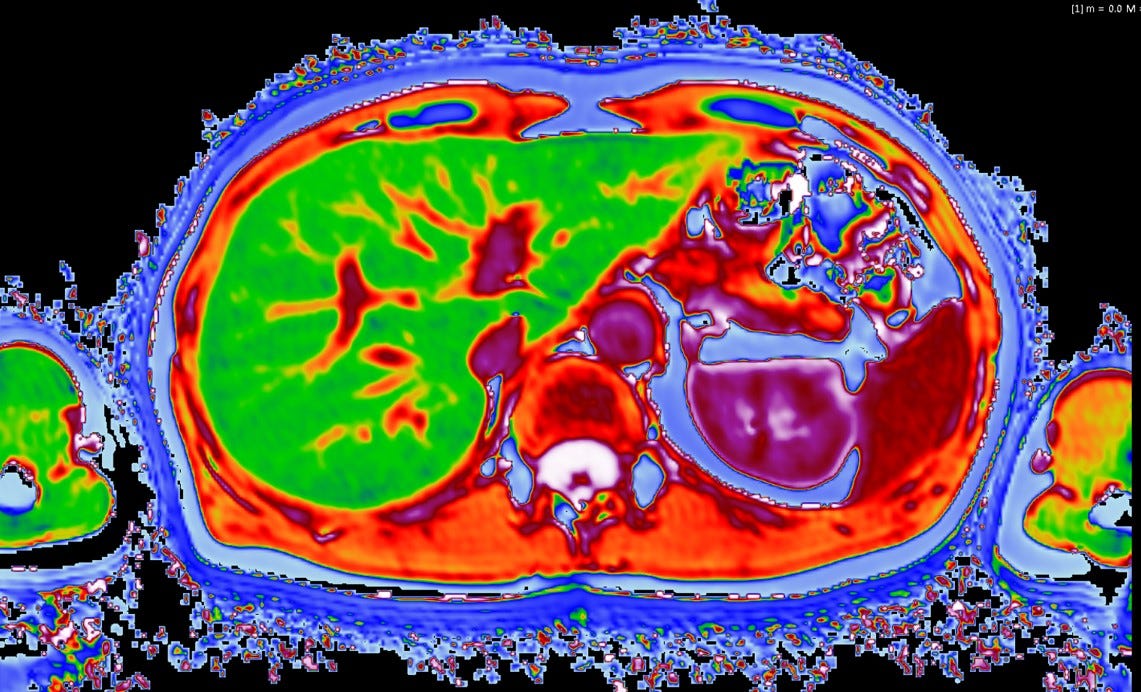

Example case. Multiparametric MRI of the prostate gland in a Multi-Parametric Mri — multiparametric mri (mpmri) of the prostate is a novel promising tool for diagnosis of prostate cancer that might. multiparametric magnetic resonance imaging. — multiparametric mri (mpmri) is an imaging modality that combines anatomical mr imaging with one or more. Risk stratification for targeted biopsy; — multiparametric mri provides detailed information on the microvascular properties of. Multi-Parametric Mri.